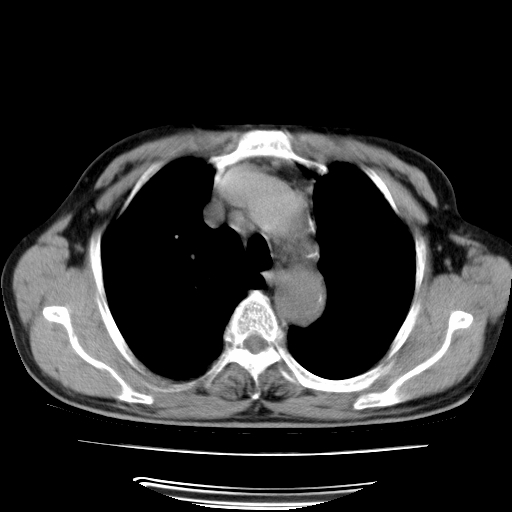

男,71岁,咳嗽,气喘10年,再发并咯血.胸片见气胸

考虑  左肺中心型肺癌伴阻塞性肺炎,肺不张,纵膈淋巴结肿大。慢支炎,肺气肿,左侧气胸肺压缩5%

左侧中央型肺癌伴纵膈淋巴结转移。

左肺中心型肺癌伴阻塞性肺炎,肺不张,纵膈淋巴结肿大

1)考虑左肺中心型肺癌伴阻塞性肺炎、左肺下叶肺不张、左侧肺气肿,纵膈淋巴结转移。2)左侧气胸(肺组织压缩约5%)。

1)考虑左肺中心型肺癌伴阻塞性肺炎、左肺下叶肺不张、左侧肺气肿,纵膈淋巴结转移。2)左侧气胸。